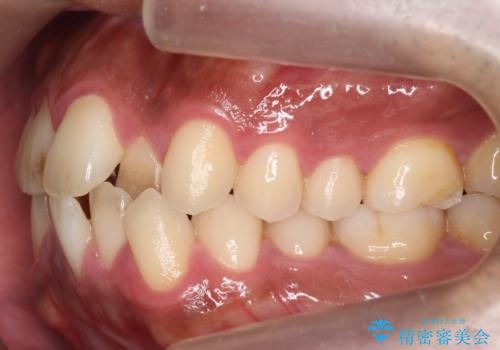

前歯が反対にかんでいる 部分ワイヤーとインビザラインの併用で短期治療

- 30代男性

- 11ヶ月

- 前歯の並びを気にして来院。

前歯が一本奥に入っているのを乗り越えるにはワイヤー矯正が治療期間も短く、歯に負担が少なく有利と説明しました。